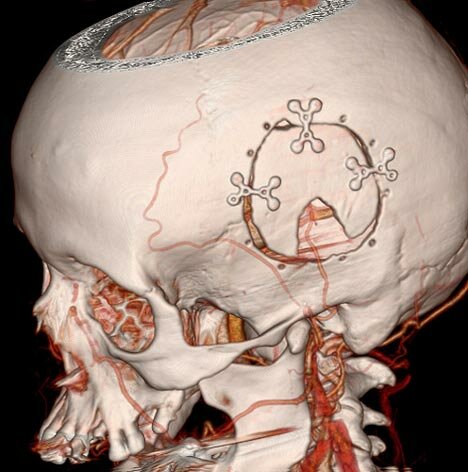

• Topografía en 3D

Topografía en 3D

Utilizado en gran manera en la radiología dental, la tecnología en 3D proveen una imagen detallada al personal medico con la capacidad de ver dicha foto tomada en forma isotrópica, o sea en ángulos frontales, hacia los lados, por debajo y por detrás.